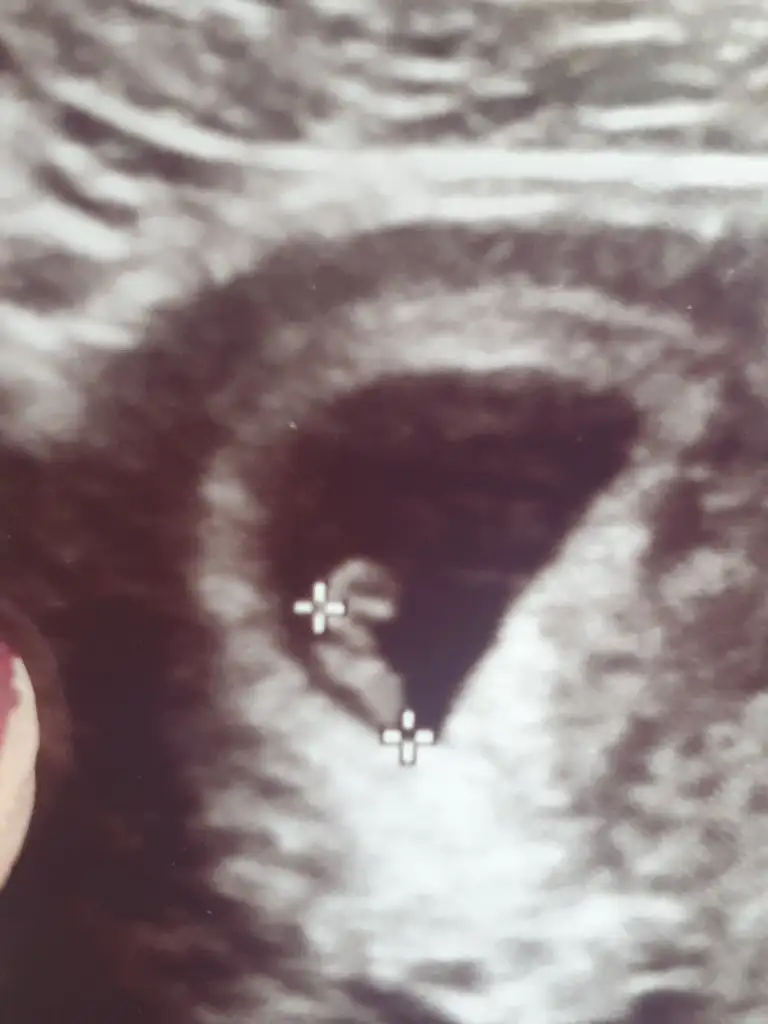

Kizlaaarr öncelikle Allah herkese bu duyguyu yaşatsın saglikla buyutsun bebelerini ben duydum bugün kalp atışını 6+6 haftalik dedi cok ritmik ve saglikli dedi cok şükür Allah'ıma cok mutluyum kizlarr🥰

• IMG-20230117-WA0003.webp

IMG-20230117-WA0003.webp

19,7 KB · Görüntüleme: 82

Ayy maşallah maşallahhh 😍 şimdi buradaki atılan rahimin hangi konumunda tutunduguna göre cinsiyet tahmini diye bir fotoğraf vardi ya ? Ona göre sizinki erkek heheheh 🤭